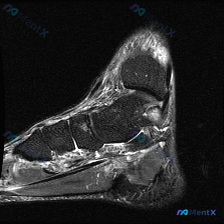

分享一例足部MRI T2加权矢状位读片,整理了完整思路和大家讨论。

本次分析的是足部MRI T2加权矢状位图像,原始问题是观察是否存在软骨异常,我们先把所有影像发现整理清楚:

- 骨骼结构:跟骨、距骨、舟骨、楔骨及跖骨结构完整,骨皮质连续,未见骨折线;骨髓信号整体正常,未见弥漫性骨髓水肿或浸润征象

- 关节软骨:足部各关节(距下关节、距舟关节、跗跖关节等)间隙清晰,未见软骨下骨质破坏,也没有明显关节积液的T2高信号,没有看到明确的软骨变薄、缺损或软骨下水肿

- 肌腱筋膜:足底筋膜可以清晰显示,从跟骨结节起点向远端延伸,关键发现:跟骨结节足底筋膜起点处可见明显T2高信号,筋膜呈梭形增厚,信号明显高于正常腱性组织,符合局部水肿、炎症或变性改变

- 软组织:皮下层次清晰,没有明显弥漫肿胀或脓肿征象